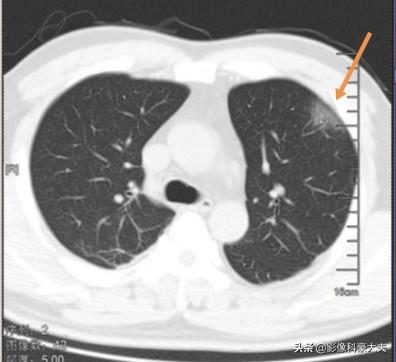

ヒトの肺胞の壁には、I型肺胞上皮とII型肺胞上皮の2種類の細胞がある。 今回の新型コロナウイルスは、表面に小さな突起がたくさんある王冠のような形をしており、エキノカンジンタンパク質を介してII型肺胞上皮に付着し、泥棒が鍵をこじ開けるように細胞の中に潜り込んで複製し、局所的な炎症とCT上のすりガラス状の影を引き起こす細胞死を引き起こす:

場合によっては、体が治療に対して抵抗性や感受性を持ち、病変がすぐに吸収されて良くなり、場合によっては跡形もなくなることもある。

少数の重症患者は進行し続け、病変はより大きくなり、白い肺が形成されることさえある。この重篤な疾患は高齢者、特に高血圧、糖尿病、慢性閉塞性肺疾患(COPD)の患者に多くみられる。